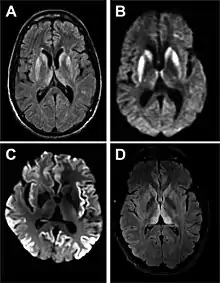

| Magnetic resonance image of sporadic CJD[2] | |

Imaging

Imaging of the brain may be performed during medical evaluation, both to rule out other causes and to obtain supportive evidence for diagnosis. Imaging findings are variable in their appearance, and also variable in sensitivity and specificity.[43] While imaging plays a lesser role in diagnosis of CJD,[44] characteristic findings on brain MRI in some cases may precede onset of clinical manifestations.[45]

Brain MRI is the most useful imaging modality for changes related to CJD. Of the MRI sequences, diffuse-weighted imaging sequences are most sensitive.[46] Characteristic findings are as follows:

- Focal or diffuse diffusion-restriction involving the cerebral cortex and/or basal ganglia. In about 24% of cases DWI shows only cortical hyperintensity; in 68%, cortical and subcortical abnormalities; and in 5%, only subcortical anomalies.[47] The most iconic and striking cortical abnormality has been called "cortical ribboning" or "cortical ribbon sign" due to hyperintensities resembling ribbons appearing in the cortex on MRI.[48] The involvement of the thalamus can be found in sCJD, is even stronger and constant in vCJD.[49]

- Varying degree of symmetric T2 hyperintense signal changes in the basal ganglia (i.e., caudate and putamen), and to a lesser extent globus pallidus and occipital cortex.[44]

- Cerebellar atrophy